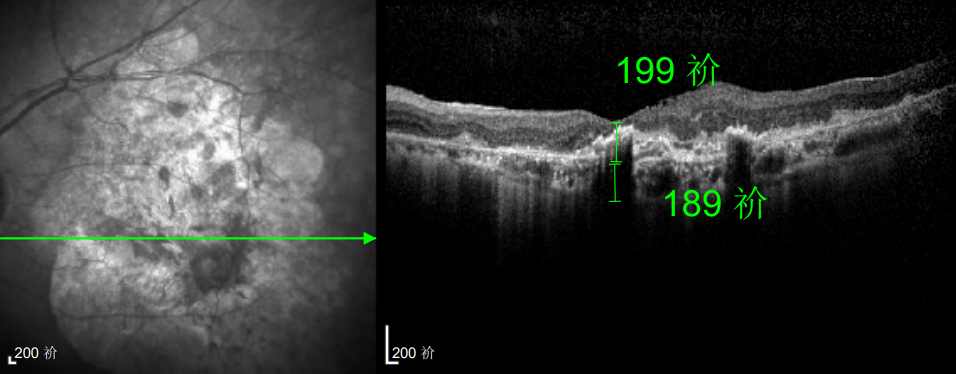

幸运的是,三年后的一次例行复查中,医生通过眼底监测及时发现林婆婆的右眼眼底病变问题,确诊为湿性老年性黄斑变性。得益于定期筛查的及时性,王晓波主任第一时间为她启动治疗,最终成功将右眼矫正视力稳定在0.8左右。

如今,林婆婆依然坚持每半年进行一次巩固治疗,谈及右眼的好视力,她感慨道:“全靠听话遵医嘱,不然现在可能早就看不清东西了。”

王晓波主任指出,尽管近十年来林婆婆的右眼接受了多次注射治疗,但全程遵循规范诊疗方案,病情得到有效控制,成功维持了良好视力。反观临床中不少黄斑变性患者,因治疗不规范,最终陷入低视力困境,视力损伤难以挽回。